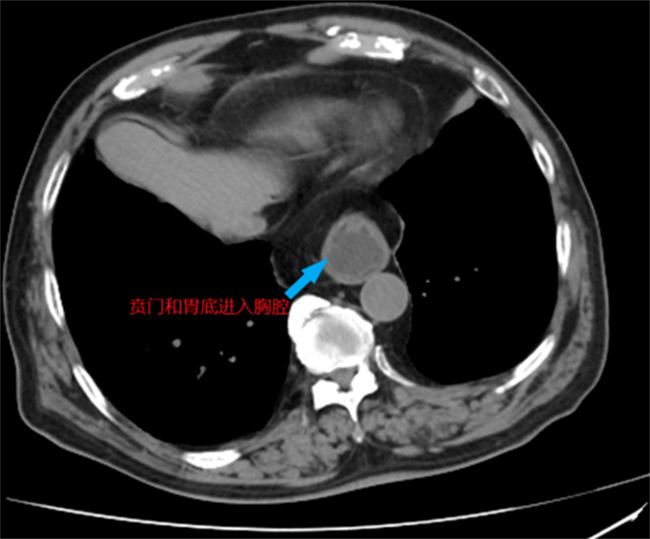

多年来,吴阿伯一直将烧心、反酸等症状归咎于胃病。他不断服用胃药,但效果甚微,症状反复出现。最近,随着病情加重,吴阿伯开始出现呕吐的情况,不得不住进医院接受治疗。在广州中医药大学第三附属医院消化内科的主管医师郭歆的指导下,进行了详细的检查,结果显示他患有食管裂孔疝,并伴有反流性食管炎。郭医生指出,吴阿伯的症状包括嗳气、反酸和胸骨后烧灼感等,都是由于反流性食管炎引起的。由于食管裂孔疝的存在,单纯依靠内科药物治疗无法从根源上治疗病情,因此请来普外科医生协助治疗。

普外科副主任医师肖光辉及其团队为吴阿伯实施了创伤小、恢复快的微创手术。手术中,肖医生通过腹腔镜和微创手术器械,为吴阿伯进行了腹腔镜下食管裂孔疝修补术和胃底折叠术。通过在腹部打5个小孔,肖医生成功进行了微创手术。经过多学科的协同治疗,吴阿伯的症状消失,康复顺利,出院后恢复了正常的生活。